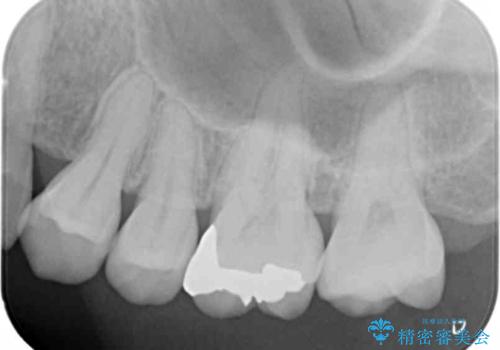

見た目よりも精度を優先したいとのことだったため、ゴールドインレーでの修復処置を行いました。

- 左上6 ゴールドインレー 77,000円費用は治療当時の料金となります

ゴールドの修復物は高い精度を出すことができるため非常に適合の良いものを装着することができます。